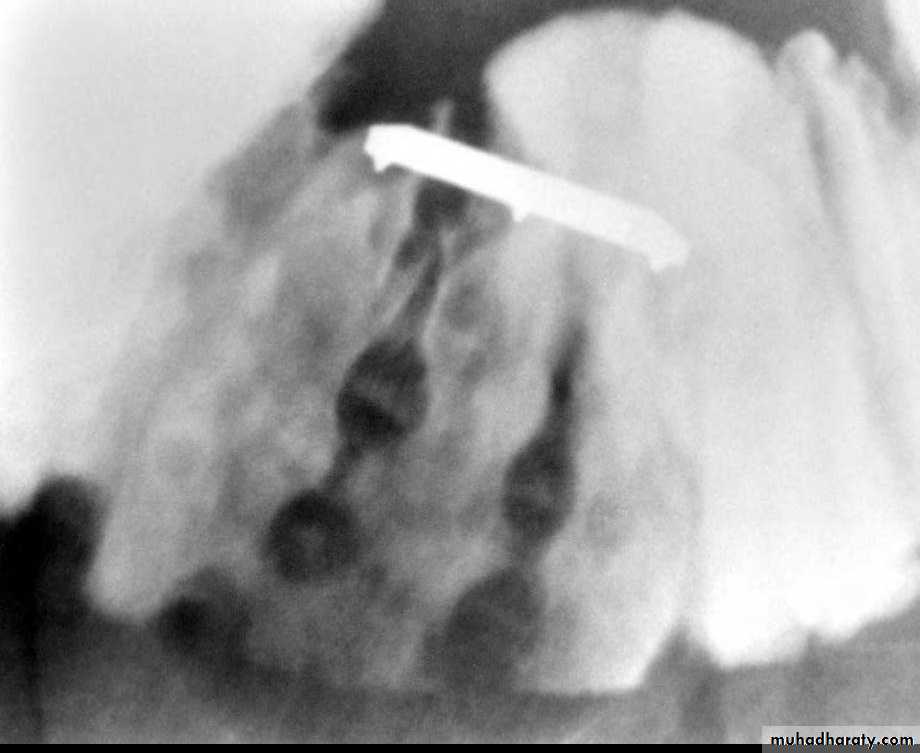

Multiple discrete ulcerations are present in the distal small bowel.

The central barium collections (ulcer crater) and mounds of edema are characteristic of aphthous ulcers.A cobblestone mucosal pattern affects a nonstenotic segment of small bowel